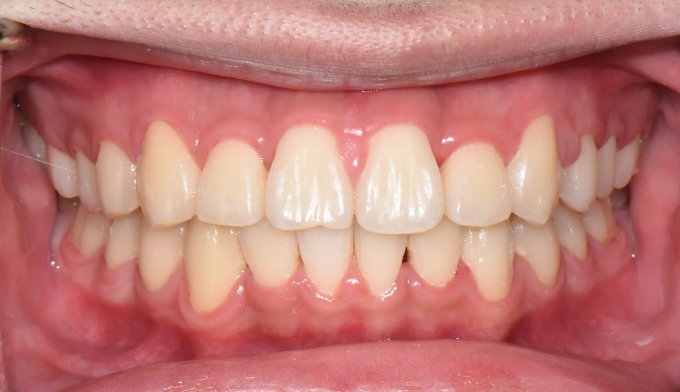

불규칙앞니

불규칙한 앞니를 교정하기 위해선 공간을 만들어야 합니다.

악궁이 좁은 경우에는 확장치료를, 그렇지 않으면 전체 치아를 후방이동시키거나 치아를 삭제하기도 합니다.

이번에는 악궁이 좁은 경우에 해당됩니다. 그 정도가 심해, 윗니 일부가 아랫니보다 안쪽으로 들어가있습니다.

상악확장장치를 통해 악궁을 넓혀주고 치아를 배열해줍니다.

치료기간은 15개월 소요되었습니다.